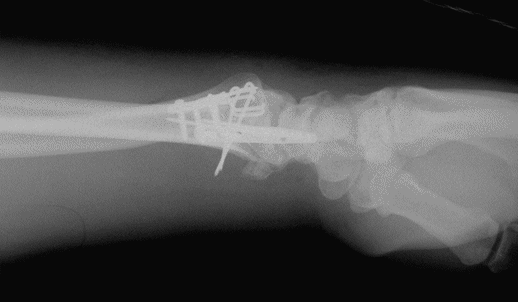

Case 1 Injury

Case 1 Postop